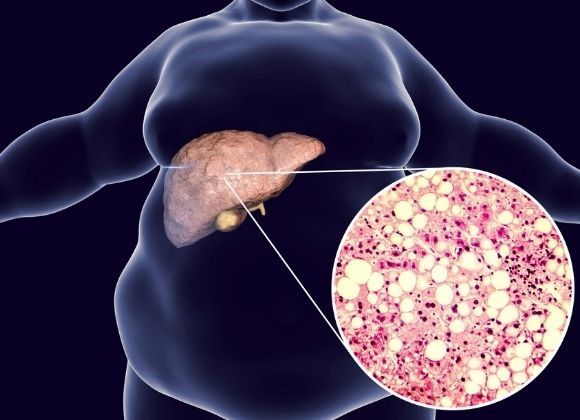

• Ztukovatělá játra

Ztukovatělá játra

Játra

Trpí také játra, jelikož i v ní se při obezitě začínají ukládat tuky. Ztukovatění jater má pak za následek zvětšení jater, pocit plnosti a tlaku v břiše, sníženou výkonnost a zvýšenou únavu.